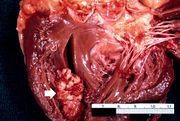

| 16:27, 19 August 2013 | IPLab4MuralThrombus1.jpg (file) | 60 KB | Seung Park | This is a gross photograph of the heart from this case demonstrating the well-formed thrombus (arrow) tightly attached to the myocardium near the apex of the left ventricle. | 1 | |